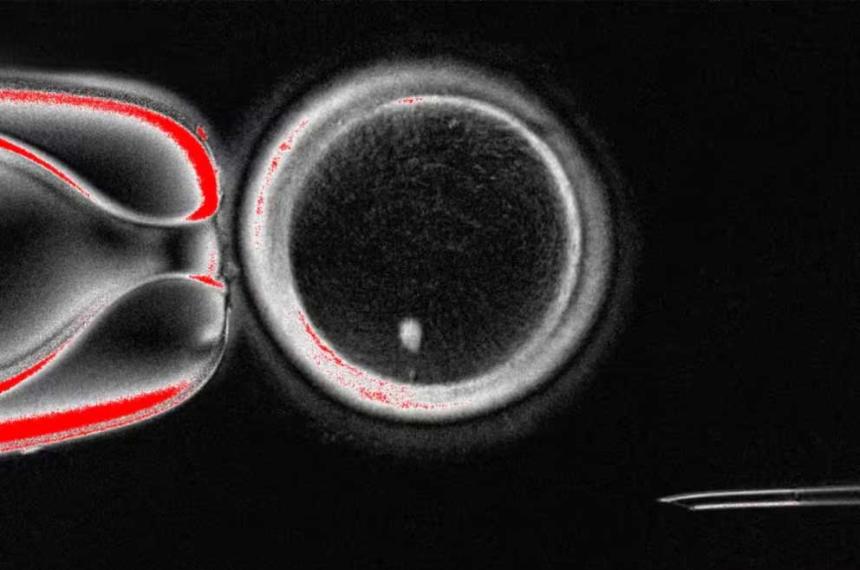

El cambio llegó con el desarrollo de la técnica ASA-PD (Advanced Sensing of Aggregates for Parkinson's Disease), un método de microscopía de fluorescencia ultrasensible que "amplifica" la señal de los oligómeros. Steven F. Lee, investigador de la Universidad de Cambridge y autor principal del trabajo, explicó: "Durante mucho tiempo se sospechaba que estos cúmulos estaban presentes, y este estudio ayuda a confirmarlo. Se trata de un paso importante, ya que poder verlos permite que los investigadores comprendan cómo contribuyen a la enfermedad".

Tras analizar 1,2 millones de nanoagregados en muestras de cerebros, los científicos detectaron un patrón clave: los oligómeros estaban presentes en todos los cerebros, pero en los pacientes con Parkinson se mostraban más grandes, brillantes y abundantes. Incluso, se detectó un subtipo que solo aparecía en quienes padecían la enfermedad, lo que podría funcionar como un marcador temprano.